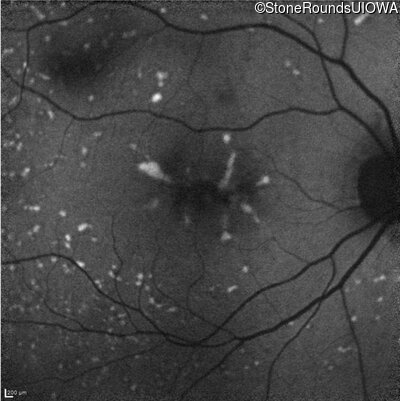

Infrared Fundus Photograph - Right - 20/20

Exemplar